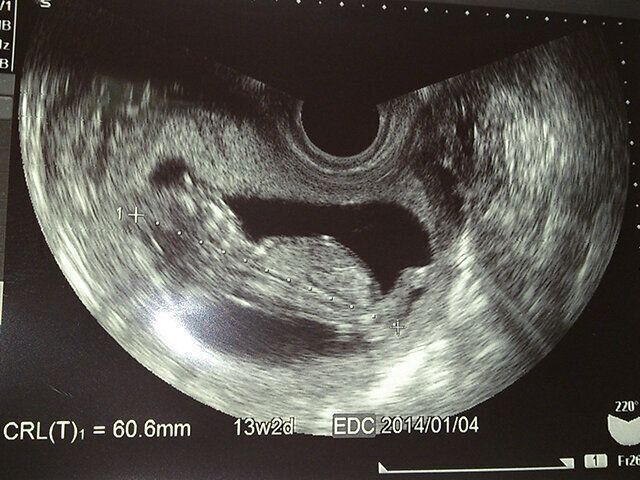

「2人は夫との婚約と同時に、自然妊娠で私たちのもとに来てくれました。経腟エコーでは、胎児は1人しか見えず、エコー写真にも1人しか写っていませんでした。ところが妊娠4カ月頃、おなかの上からエコーをするようになった時に先生が『ん?あれ?おかしいな……ちょっと待ってね……頭が2つあるな……』と言うのです。先生が戸惑う姿を見ながら私は『えっ?何?それって1つの体に頭が2つあるってこと?結合双生児ってこと?』と一気に血の気が引いたのを覚えています。しかし『あれ?ちゃんと背骨も2つあるね……これは双子ちゃんですかね?』という声が聞こえ、“双子”という夢にも思わなかった言葉にびっくり。しばらくその状況について行けず放心状態だったのを今でも思い出します。その後、身体はちゃんと離れていたことがわかり『この大きさまで双子だと分からなかったなんて!』と先生も驚いている様子でした。双子出産には色々なリスクがあるということで、群馬県にある大きな総合病院を紹介してもらい、そこに通院するようになりました」(良美さん)